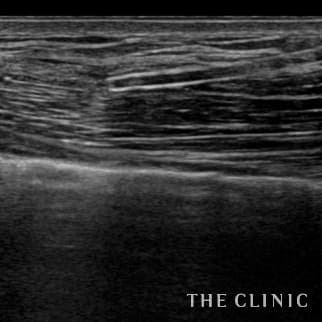

35歳 女性 アクアフィリング(アクアリフト)豊胸のお悩みのアクアフィリング(アクアリフト)豊胸除去

コンデンスリッチ豊胸を行うために、前もってアクアフィリングの除去を行いました。エコーで確認するとかなり厚い被膜が形成されています。 アクアフィリングは生理食塩水で溶解されるとのことで、エコー下に生理食塩水を注入しましたが、なかなか溶解できず、ヒアルロニダーゼも追加してなんとか溶解除去することができました。右側は炎症があった為か、汚く濁った状態でした。治療の概要 アクアフィリング除去+コンデンスリッチ豊胸:乳腺用エコーを用いて、バスト内の状態を確認。その後、生理食塩水でアクアフィリングを溶解する。溶解仕切れない場合には、注射器で吸い出し除去。アクアフィリング の除去後、バストの皮下にコンデンスリッチファット(老化細胞や不純物を取り除いて濃縮させた自己脂肪)を注入。 施術費用 アクアフィリング 除去(会員料金):¥600,000(税込¥660,000)/溶解1部位